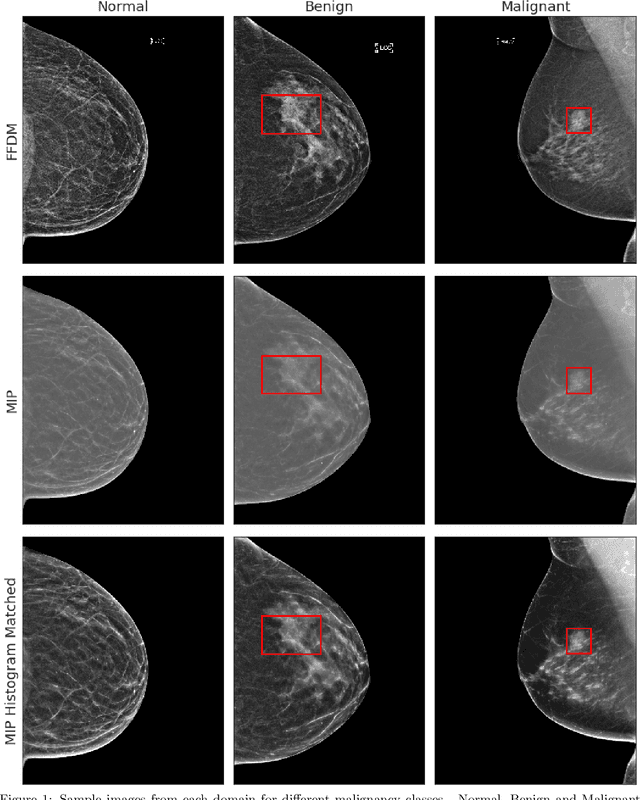

Abstract:Mammography-based screening has helped reduce the breast cancer mortality rate, but has also been associated with potential harms due to low specificity, leading to unnecessary exams or procedures, and low sensitivity. Digital breast tomosynthesis (DBT) improves on conventional mammography by increasing both sensitivity and specificity and is becoming common in clinical settings. However, deep learning (DL) models have been developed mainly on conventional 2D full-field digital mammography (FFDM) or scanned film images. Due to a lack of large annotated DBT datasets, it is difficult to train a model on DBT from scratch. In this work, we present methods to generalize a model trained on FFDM images to DBT images. In particular, we use average histogram matching (HM) and DL fine-tuning methods to generalize a FFDM model to the 2D maximum intensity projection (MIP) of DBT images. In the proposed approach, the differences between the FFDM and DBT domains are reduced via HM and then the base model, which was trained on abundant FFDM images, is fine-tuned. When evaluating on image patches extracted around identified findings, we are able to achieve similar areas under the receiver operating characteristic curve (ROC AUC) of $\sim 0.9$ for FFDM and $\sim 0.85$ for MIP images, as compared to a ROC AUC of $\sim 0.75$ when tested directly on MIP images.